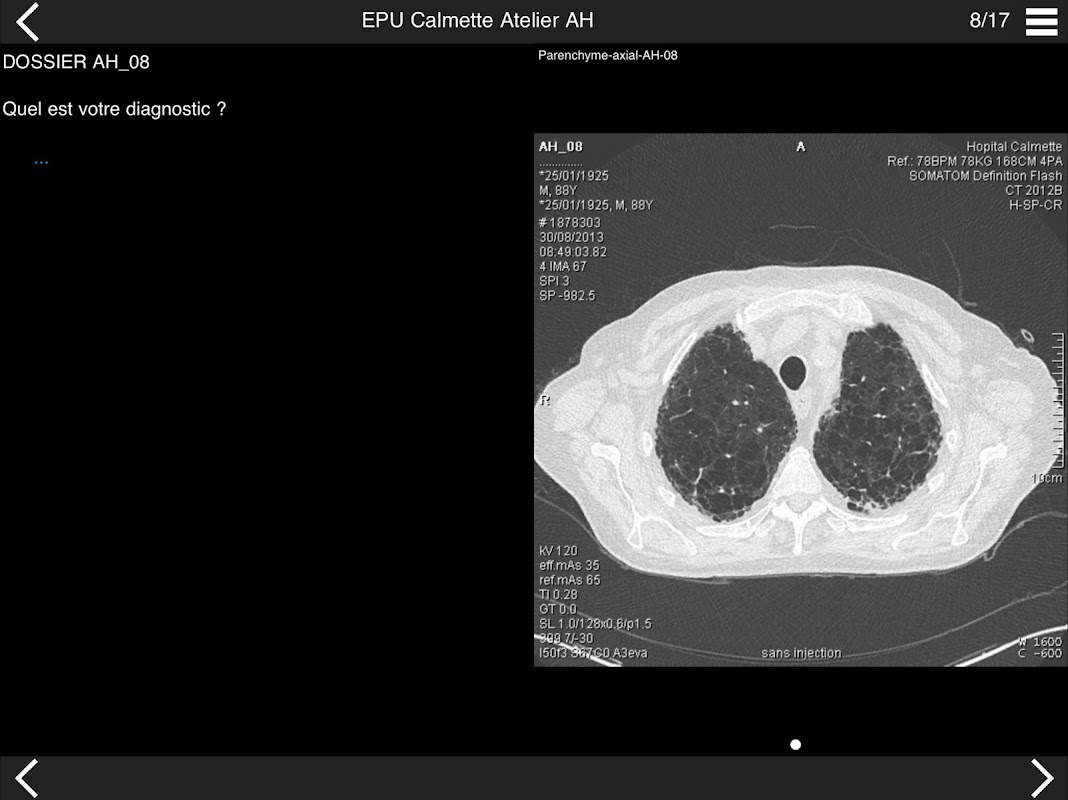

Retrouvez les cas cliniques du Cours intensif de TDM multicoupe du thorax dans cette application.

Thèmes du cours 2017 :

• DE LA SéMIOLOGIE AU COMPTE-RENDU

* BPCO et nodules pulmonaires : recommandations en 2017

* Pathologie interstitielle : lésions élémentaires et « patterns »

* Pathologie vasculaire et médiastinale

* Oncologie thoracique : bilan standard et introduction à l’étude de l’angiogénèse